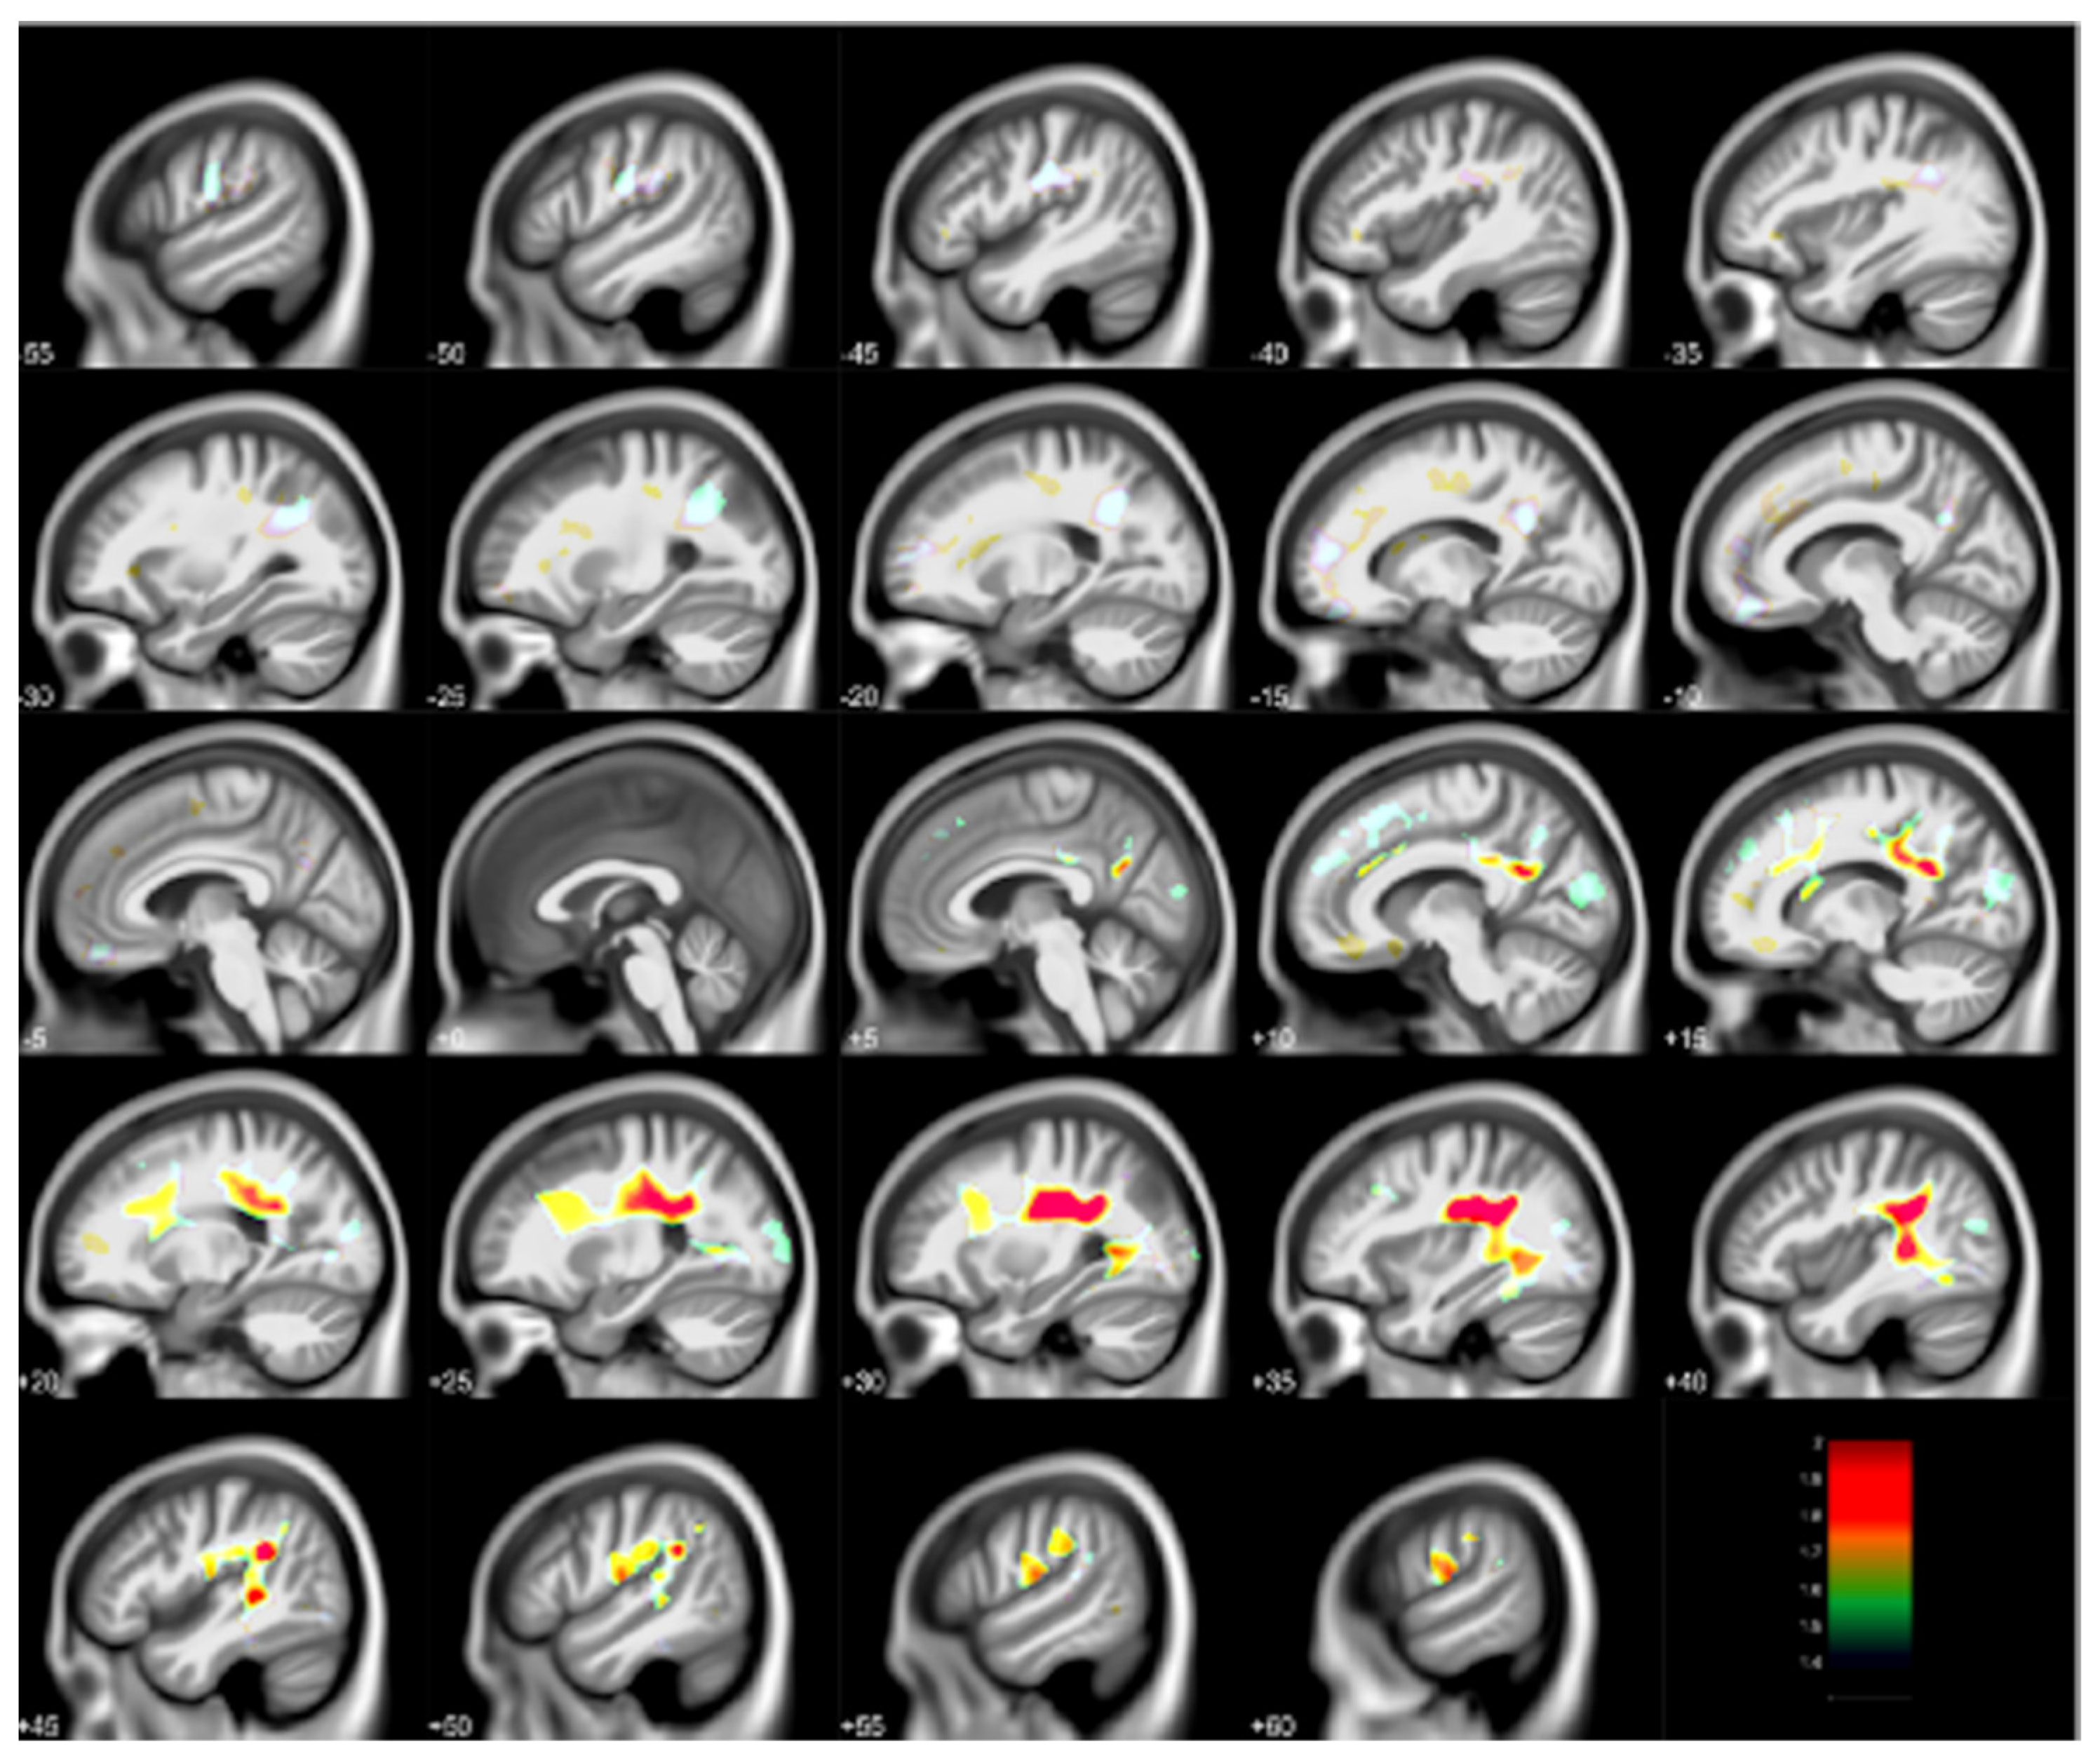

- Beckwith, T.; Cecil, K.; Altaye, M.; Severs, R.; Wolfe, C.; Percy, Z.; Maloney, T.; Yolton, K.; LeMasters, G.; Brunst, K.; et al. Reduced gray matter volume and cortical thickness associated with traffic-related air pollution in a longitudinally studied pediatric cohort. PLoS ONE 2020, 15, e0228092. [Google Scholar] [CrossRef] [PubMed]

| Early Childhood TRAP | MRI: SPM, VBM [6] | Adolescent | Reduced gray matter volumes, cortical thickness in sensorimotor regions, cerebellum | Beckwith et al. [34] |